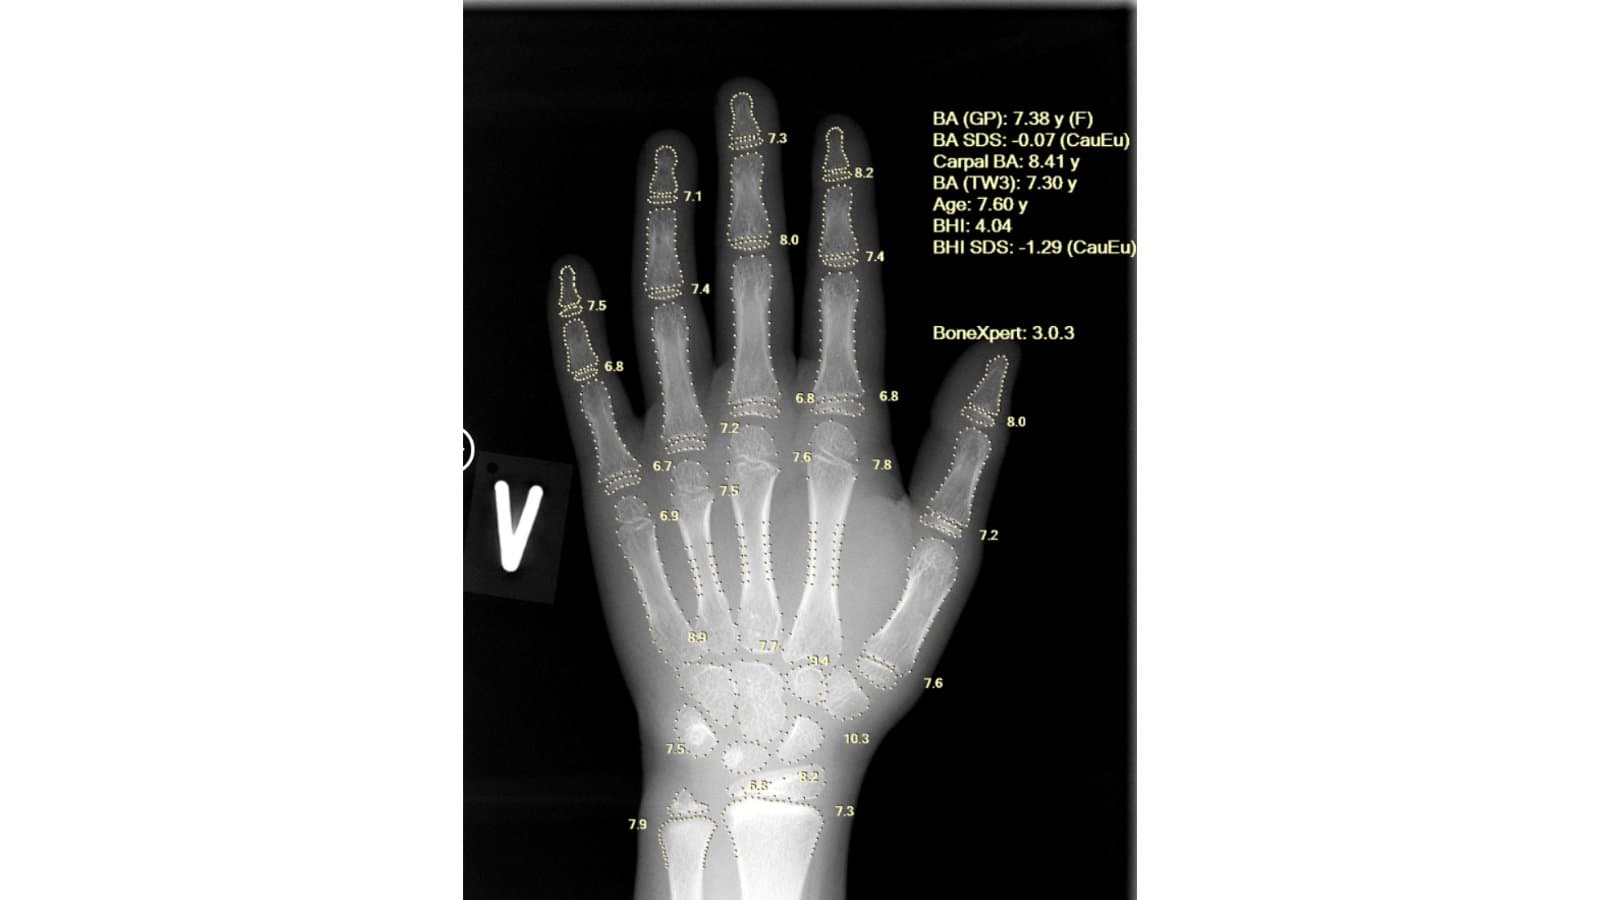

Using a single left-hand X-ray, BoneXpert provides a comprehensive, multi-method assessment that includes Greulich-Pyle (GP) bone age, Tanner-Whitehouse (TW2/TW3) bone age, carpal bone age, Bone Age Standard Deviation Score (SDS) and Bone Health Index (BHI). This depth of analysis supports early identification of constitutional growth delay and endocrine abnormalities, enabling timely clinical intervention.